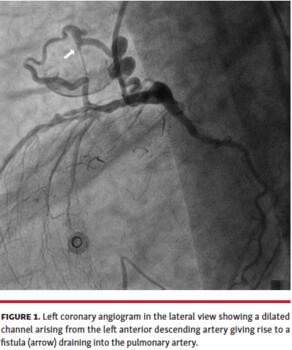

A 65-year-old man presented to our emergency department with inferior-wall myocardial infarction. Coronary angiogram revealed a completely occluded right coronary artery and significant disease in the left anterior descending (LAD) and left circumflex arteries. Left coronary artery angiogram also showed a dilated and tortuous channel arising from the LAD. A coronary-cameral fistula (CCF) was seen originating from this feeding channel and draining into another chamber (Figure 1; Video 1). The location of the receiving chamber was confirmed by positioning a Judkin’s right catheter in the pulmonary artery and repeating the angiogram in multiple views. The chamber was anterior to the ascending aorta in the lateral view and to the left in the anteroposterior view, confirming it to be the pulmonary artery. There was an insignificant step up on oximetry with a Qp/Qs ratio of 1.1, suggesting a hemodynamically insignificant shunt. Contrast-enhanced computed tomography of the coronary arteries confirmed the diagnosis of CCF and the patient was advised to undergo coronary artery bypass grafting with ligation of the CCF.